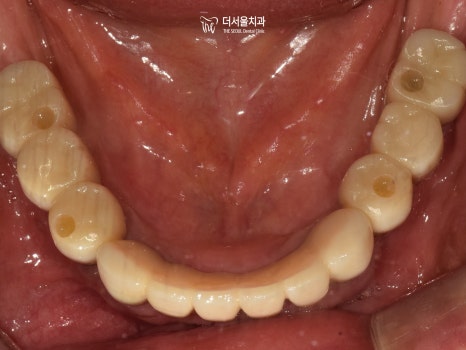

최종 보철 제작까지 미리 고려하여

픽스처의 방향, 각도를 설정해 주었습니다.

CT를 통해 확인해 보니 정확하게 심어져 있네요.

어느 정도 회복될 기간을 부여한 뒤,

ISQ 측정을 통해 심어놨던 네비게이션 임플란트 가

문제없이 안정성을 얻고 있는지 확인을 했습니다.

최종 보철을 올려도 충분한 측정치가 나왔기 때문에

크라운 제작을 위한 본뜨기 과정까지 도와드렸습니다.